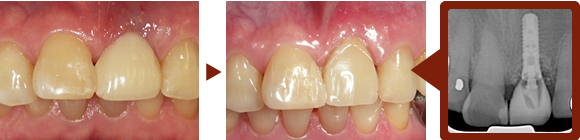

治療例

インプラント治療の流れ

歯が抜けたところにインプラントを埋入した後、顎の骨にしっかりと固定されるまで、3〜6ヶ月待ちます。

インプラントによるしっかりとした土台が出来たら、人工の歯を上にかぶせます。